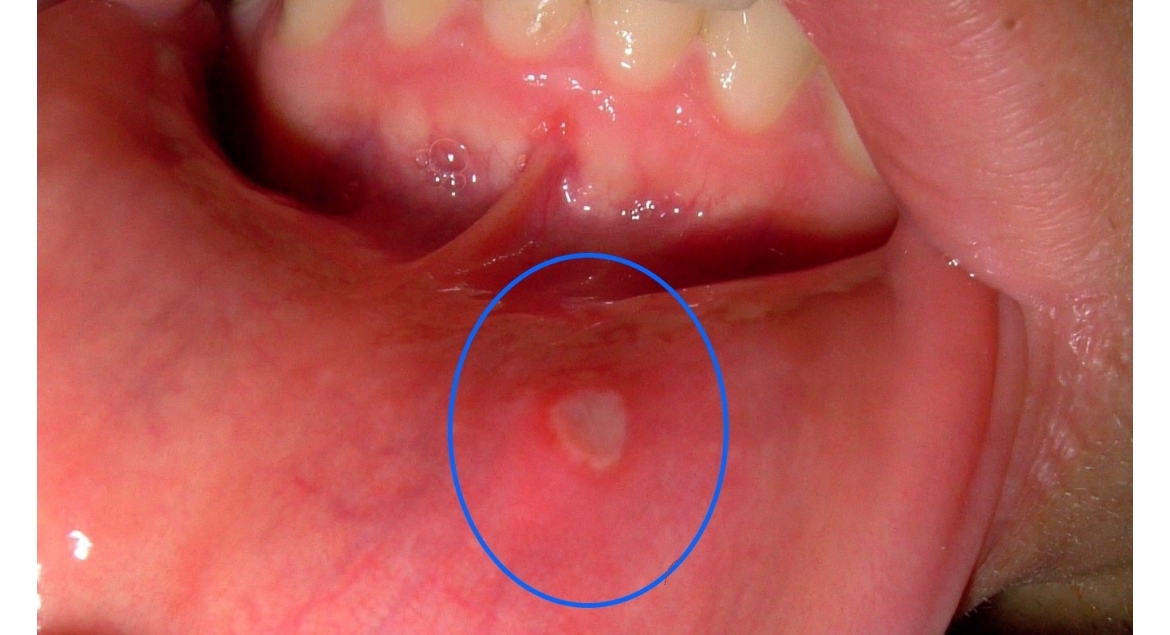

Las aftas bucales, también conocidas como úlceras bucales o estomatitis aftosa, son lesiones pequeñas y dolorosas que aparecen en el tejido blando de la boca, como en el interior de las mejillas, labios, lengua y encías. Estas lesiones pueden ser recurrentes y, aunque no suelen representar un riesgo grave para la salud, pueden afectar significativamente la calidad de vida de quienes las padecen debido al dolor e incomodidad que producen.

- Úlceras pequeñas y redondeadas, con bordes rojos e inflamados y un centro blanco o amarillo.